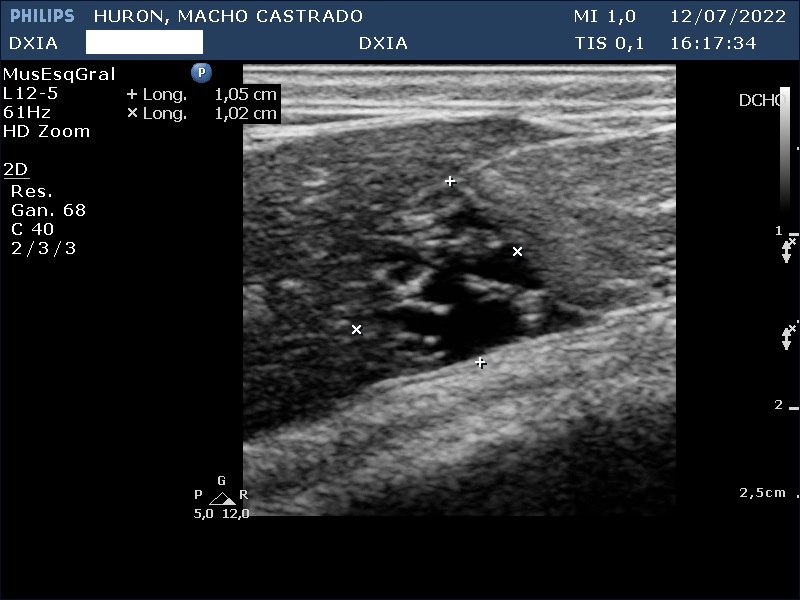

Estudio de ecografía abdominal

En esta ocasión os queremos presentar el caso de hurón (macho castrado) al que, debido a los síntomas que presentaba, tuvimos que realizarle un estudio ecográfico abdominal.

Presenta convulsiones así como hipoglucemias con picos de hiperglucemia por lo que su veterinario decide realizar un estudio de ecografía abdominal.

Hallazgos ecográficos